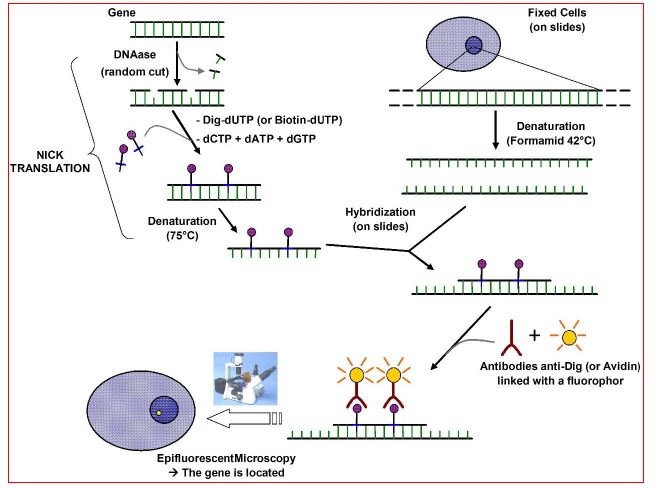

Fluorescent In Situ Hybridization) FISH)

تقنية مختبرية تستعمل في الوراثة الخلوية للكشف وايجاد تواليات معينة من DNA على الكروموسوم ، وبعض الاحيان تستعمل للكشف عن جزيئات RNA ، وتعتمد التقنية على تعريض الكروموسوم الى مجس صغير من DNA الذي حمل او الصقت به صبغة متفلورة تعطي الضوء عند استعمال مجاهر الفلورة ، وتكون النماذج في انسجة او خلايا مثبتة :